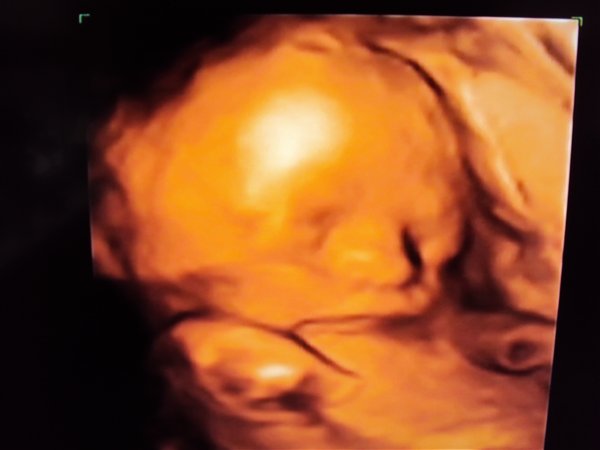

Vi fik afvide at han vejede 1 kg. her i uge 26 (25+4) Så han er en stor dreng. Han havde allerede fået deller og et tygt lag fedt på kroppen. Hun fortalte han formentlig ville være 4 kg. hvis han blev født til tiden, og ville bruge str. 56.

Sikke en dejlig dreng vi har der, og vi kan alle tydeligt se han har min mund. Hans tær er efter hans far - der var nemlig en af tærene der var lidt længer end de andre, hvilket min mand også har

Ellers kunne hun fortælle at næsen var meget lille og fin, og han allerede havde fået hår på hovedet.